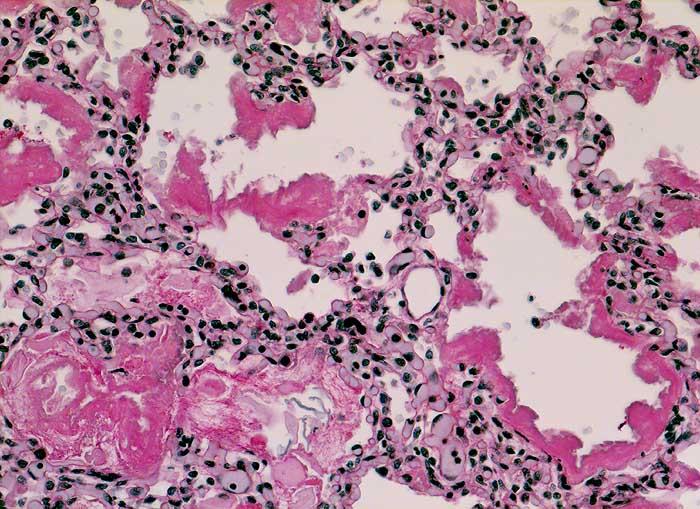

Hyaline Membranenkrankheit (IRDS)

Massive Mekoniumaspiration: Mekonium in einzelnen Alveolarräumen. Die Alveolarsepten sind austapeziert von PAS positiven hyalinen Membranen.

Normalgewichtiges Neugeborenes der 37. SSW. Linksbetonte Hypoplasie beider Lungen. Lungen vor allem im alveolären Stadium.

Kongenitale beidseitige Diaphragmahernie bekannt seit 24. Schwangerschaftswoche.

Asphyxie bei Hypoplasie beider Lungen.